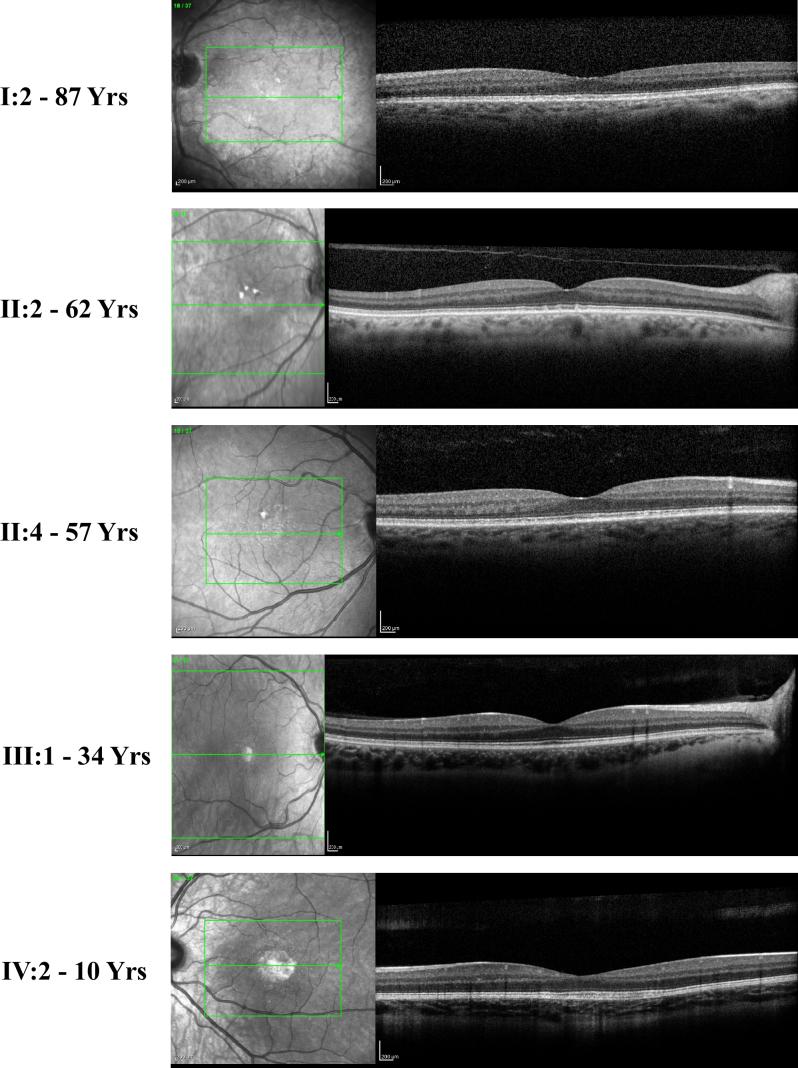

North Carolina macular dystrophy (NCMD) is an autosomal dominant maculopathy that is considered a non-progressive developmental disorder with variable expressivity. Our study aimed to clinically and genetically characterize macular dystrophy in a family (MOL1154) consisting of six affected subjects with a highly variable maculopathy phenotype in which no correlation between age and severity exists.

WES analysis performed on DNA samples from two individuals revealed a heterozygous deletion of six nucleotides [c.2247_2252del; p.(Leu750_Lys751del)] in the gene. Co-segregation analysis revealed that five of the six NCMD affected subjects carried this deletion, while one individual who had a relatively mild phenotype compatible with dry age-related macular degeneration (AMD) did not carry it. We subsequently analyzed the upstream region of that has previously been reported to be associated with NCMD and identified a unique heterozygous transversion (chr6:100040974A>C) located within the previously described suspected control region in all six affected individuals. This transversion is likely to cause NCMD.

NCMD has a wide spectrum of clinical phenotypes that can overlap with AMD, making it challenging to correctly diagnose affected individuals and family members. The DNA sequence variant we found in the gene of some of the affected family members may suggest some role as a modifier gene. However, this variant still does not explain the huge phenotypic variability of NCMD and needs to be studied in other and larger populations.